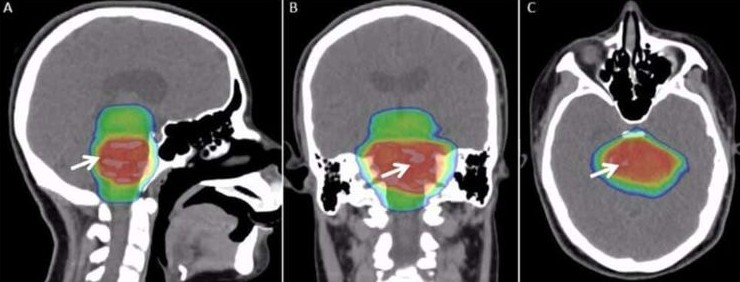

5. Причиной мучительной икоты у мужчины оказалась опухоль мозга

Икота кажется безобидным и временным явлением, но для Криса Сэндса она превратилась в настоящую пытку. Его приступы длились месяцами: в особо тяжёлые моменты икота повторялась каждые две секунды на протяжении 14 часов подряд. Он потерял работу, отношения и надежду на нормальную жизнь.

Поначалу врачи не могли найти причину и даже предположили психологическую природу проблемы. Лишь спустя несколько лет, во время съёмок телепередачи, МРТ выявило опухоль на стволе головного мозга. В 2009 году Сэндсу провели операцию, которая спасла ему жизнь. После удаления опухоли икота постепенно прекратилась.

Этот случай — не единственный. Например, Чарльз Осборн из Айовы икал без остановки на протяжении 68 лет, и причина его состояния так и осталась неизвестной.